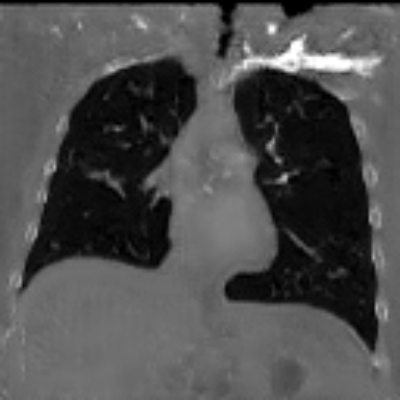

| Axial | Coronal | Sagittal | |

| X2CTGAN | ![]() |

![]() |

|

| DX2CT | ![]() |

| Ground-truth | ![]() |

Figure 3 and Table I(a) using biplanar X-rays show that proposed DX2CT can outperform three existing SOTA methods. Figure 3 shows that DX2CT can provide more accurate overall shapes and details compared to the existing methods. The quality of reconstructed CT slices in the axial plane is less satisfactory than those in the other planes. The reason is that the axial plane is perpendicular to the planes of biplanar X-rays so there exists less spatial (i.e., depth) information in the axial plane. Without using the perceptual loss [33], proposed DX2CT gave comparable LPIPS results with PerX2CTs using [33] in training. Compare their LPIPS results in Table I(a).